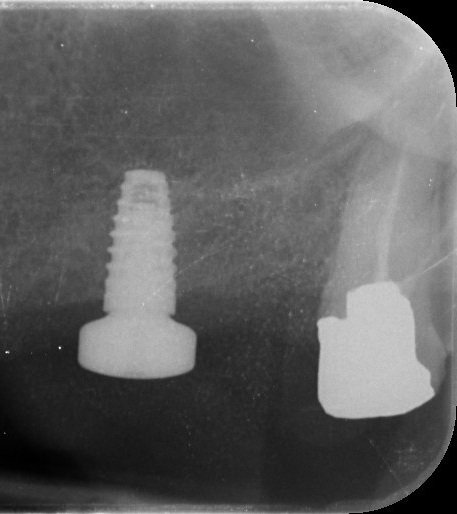

2. What option can be selected regarding the implant seen in this X ray?